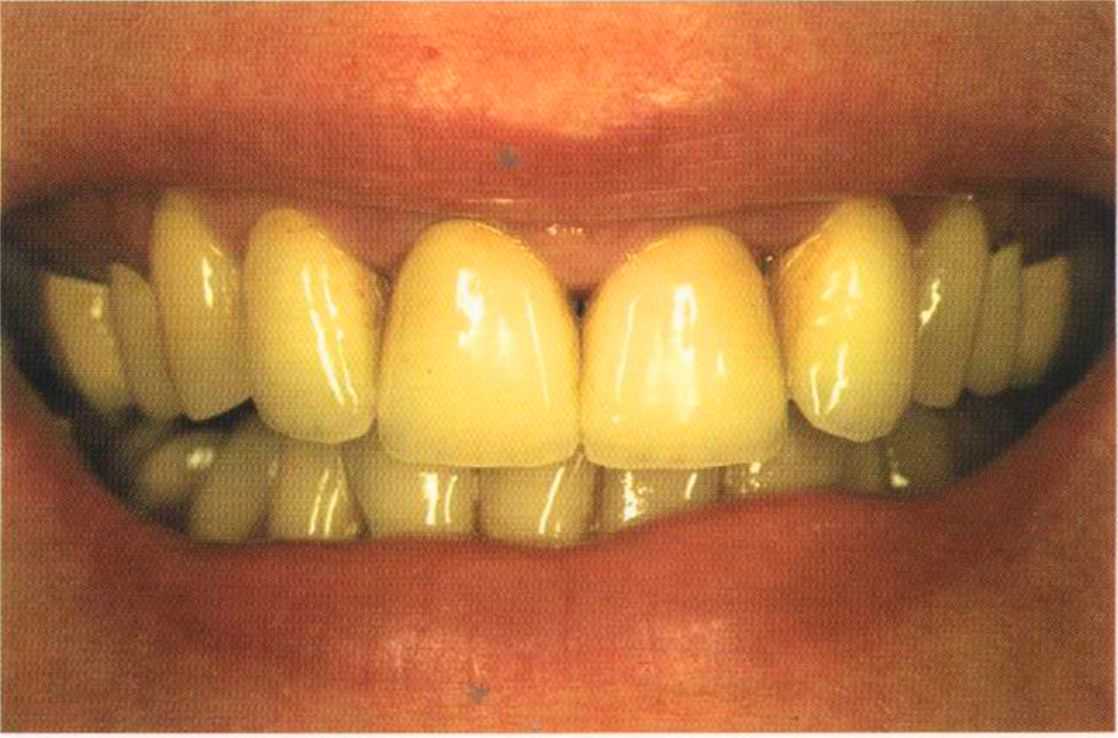

Эта женщина пришла в клинику доктора Лангханке с металлокерамической реставрацией.

Ей не нравились типичные в таких случаях темные края коронок и опаковость керамики.

Цвет 1М1 до 1М2 основной цвет в данном случае.

Коронки выполнялись в моей лаборатории вместе с пациентом. Мы работали долгих четыре часа, чтобы всем понравился результат. Обратите внимание на отражение света по краевым валикам. Мезиальные валики коронки 12 зуба гармонично переходят в дистальные валики 42 зуба. В идеальном варианте «отражающиеся валики» должны проходить по прямой линии. Это привило для всех мезиальных и дистальных валиков фронтальной группы зубов. Оно имеет очень важное значение и влияет на результат нашей работы.

Эти валики проходят перемещаясь, однако по одной линии. Примером здесь являются мезиальные поверхности на коронке 11 и на 31.